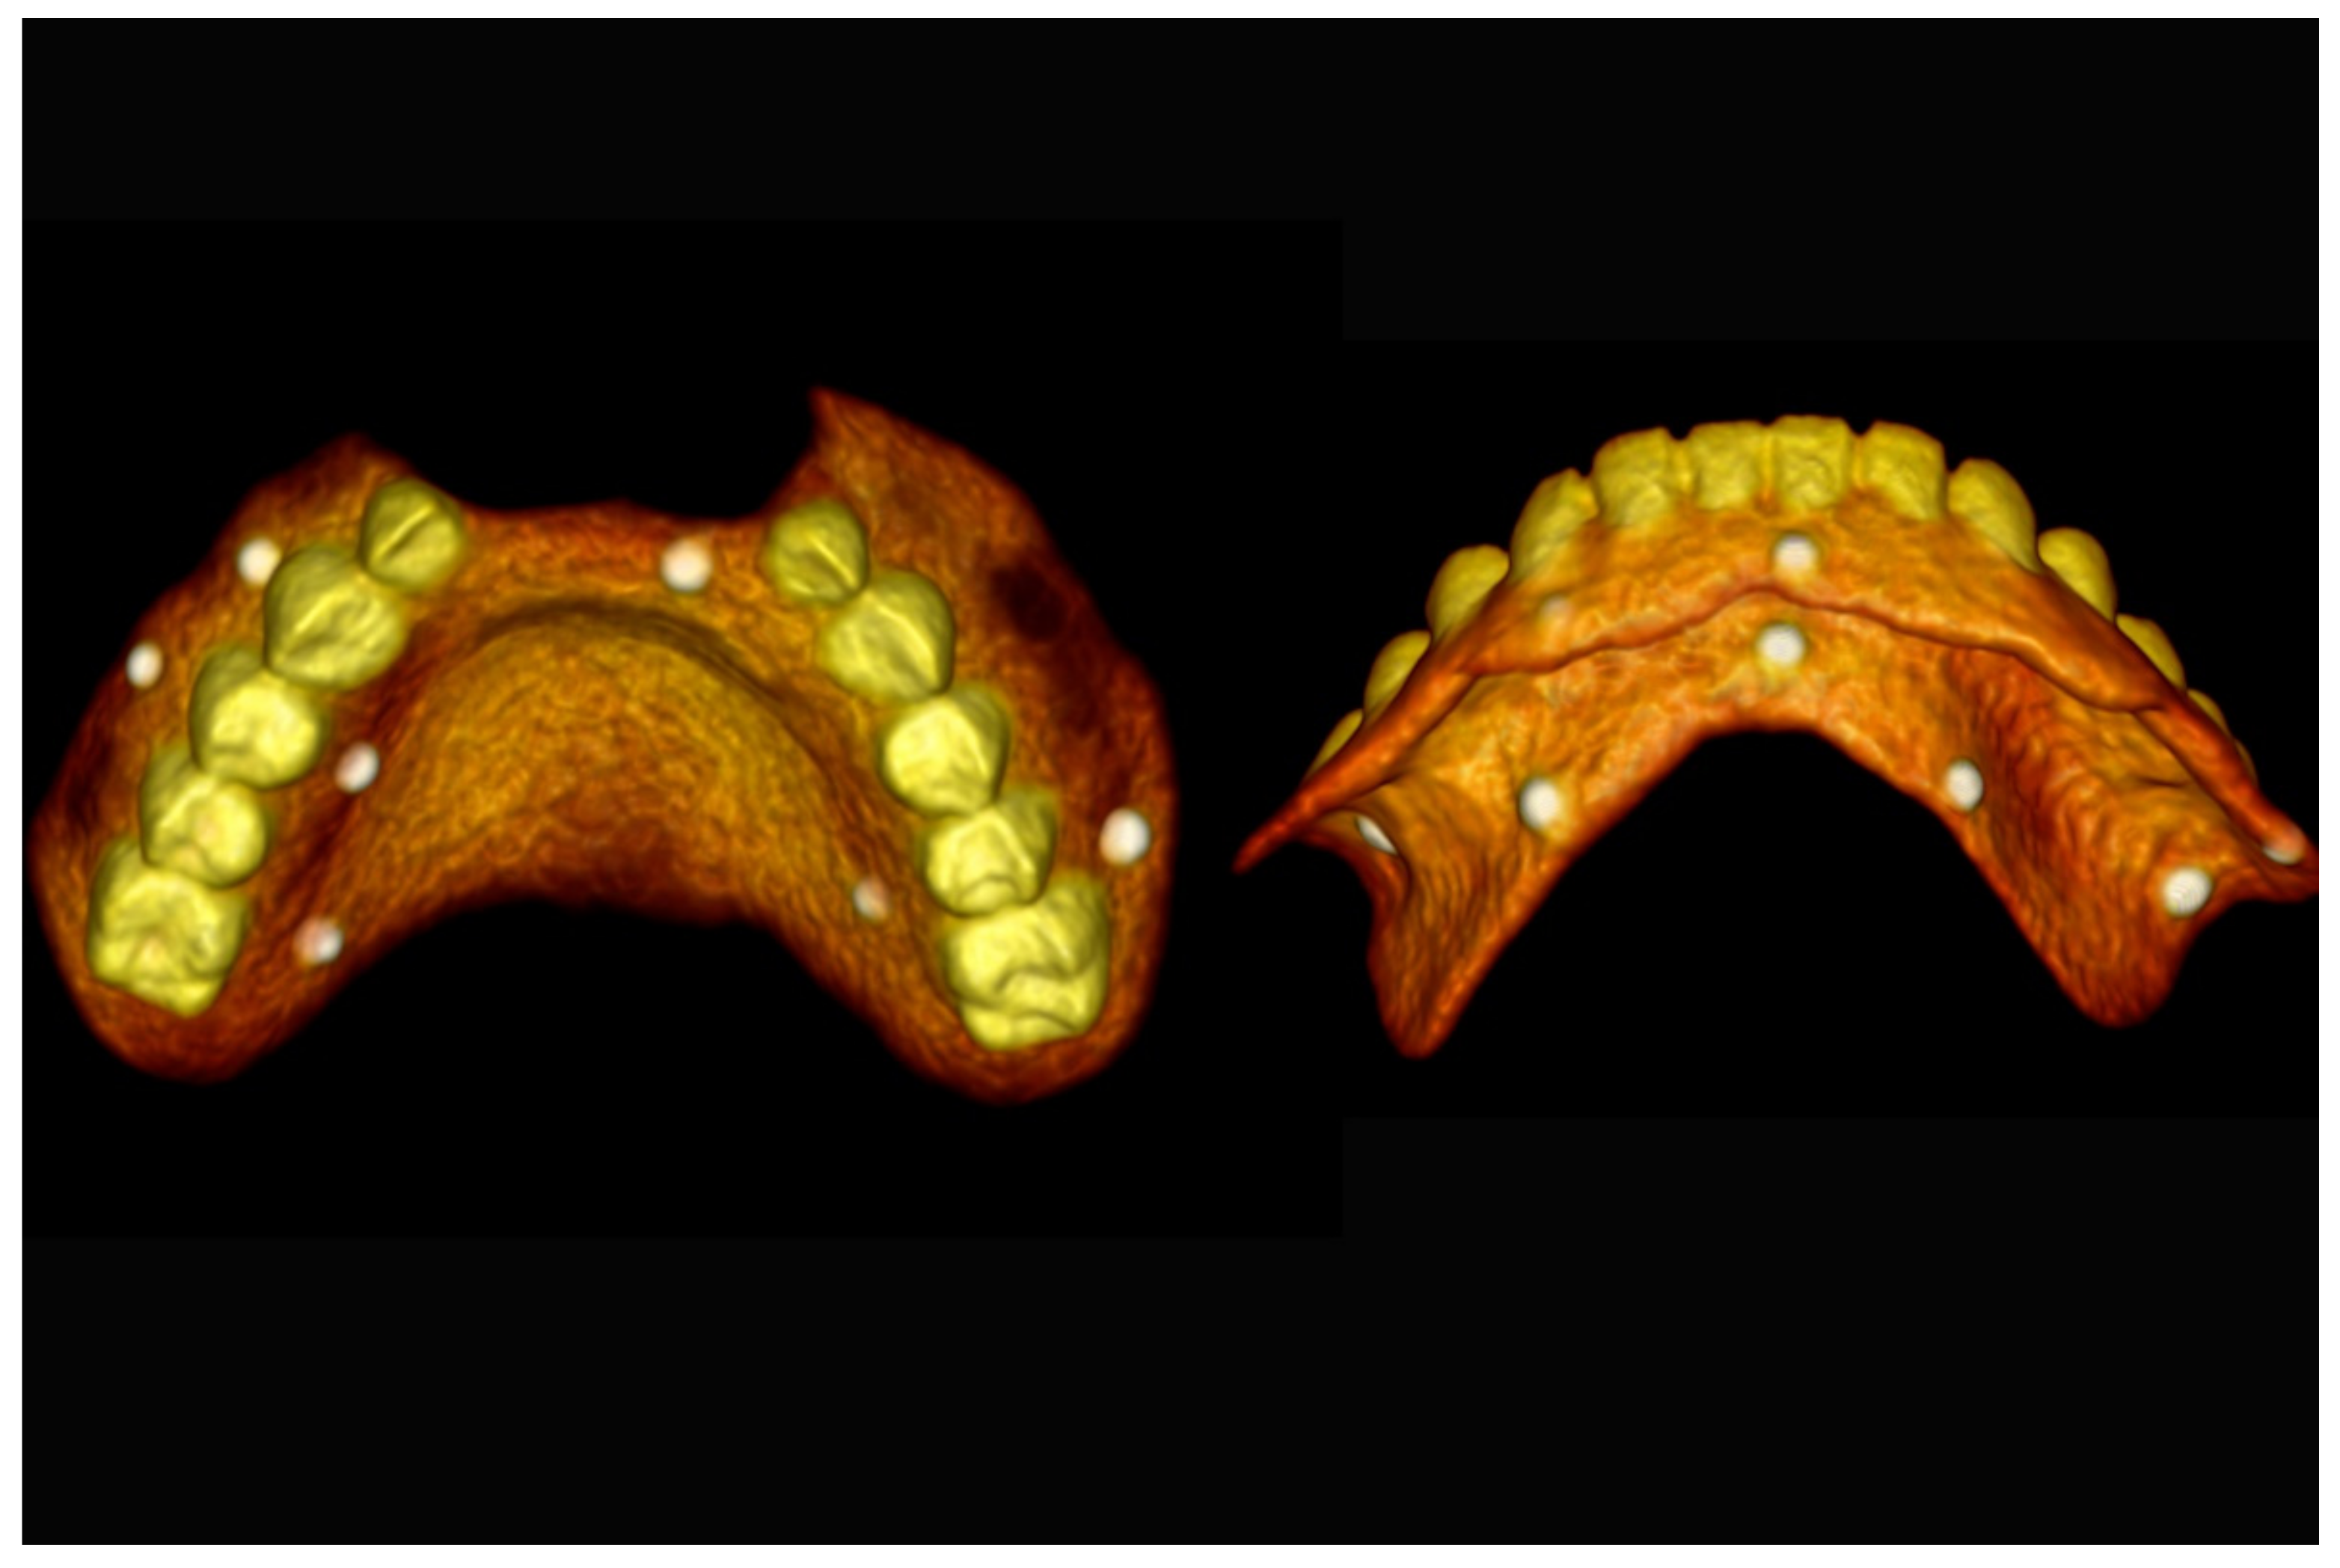

The number, the length, the diameter and the placement of computational virtual implants were determined with respect to the design of the final prosthesis the available residual bone volume and the anatomical limitations according to the previously described technical procedure (Figure 16, Figure 17, Figure 18, Figure 19, Figure 20 and Figure 21).

Figure 18.

Three-dimensional (3D) planning of the number, the diameter and the axis of dental implants with respect to the design of the final virtual maxillary prosthesis.

Figure 19.

Figure 20.

Maxillary and mandibular virtual surgical drilling guides designed according to the implant position.